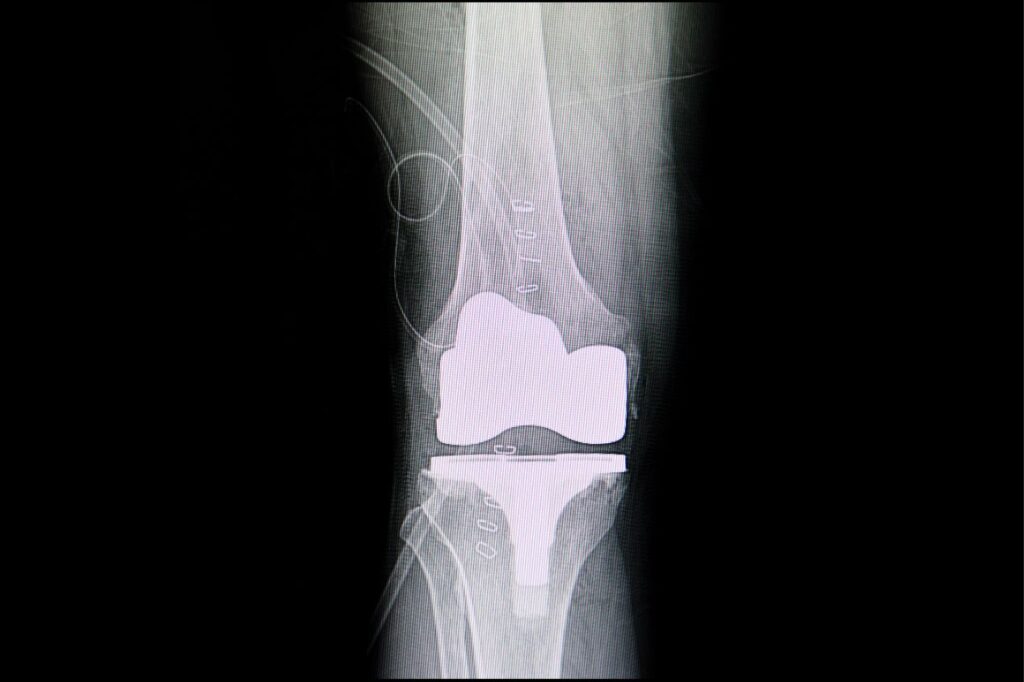

Η αρθροπλαστική του γόνατος είναι μια χειρουργική επέμβαση που εκτελείται για την αντικατάσταση της φυσικής άρθρωσης  του γόνατος που έχουμε με μια τεχνητή  επιφάνεια άρθρωσης. Αυτή η νέα άρθρωση η οποία αποτελείται από υψηλής ποιότητας τιτάνιο εφαρμόζει απόλυτα στην υπάρχουσα αρθρική επιφάνεια.

Σε αυτήν την απόλυτη εφαρμογή παίζει ιδιαίτερα σημαντικό ρόλο η ρομποτική τεχνολογία στην αρθροπλαστική γόνατος. Η ρομποτική τεχνολογία βοηθάει τον χειρουργό να επιτύχει ένα πραγματικά άριστο αποτέλεσμα σε τρία στάδια.